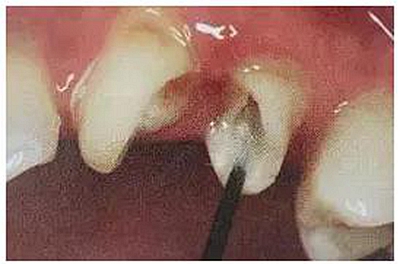

兩年前患者因?yàn)楹笱朗澄锴度驮\,檢查26殘冠,在他院做干髓治療近10年,充填材料已經(jīng)脫落,叩診輕微不適,要求治療修復(fù)。

絢彩AT無飾瓷全形態(tài)氧化鋯產(chǎn)品體驗(yàn)+全冠和嵌體微創(chuàng)修復(fù)后牙絢彩AT無飾瓷全形態(tài)氧化鋯產(chǎn)品體驗(yàn)+全冠和嵌體微創(chuàng)修復(fù)后牙舌側(cè)牙體破壞至齦下,髓腔變色明顯。26經(jīng)過與患者溝通降低咬合并做了根管治療。

絢彩AT無飾瓷全形態(tài)氧化鋯產(chǎn)品體驗(yàn)+全冠和嵌體微創(chuàng)修復(fù)后牙從側(cè)面照可以看到26牙體變黑,頰側(cè)壁不足2mm,牙質(zhì)脆弱。